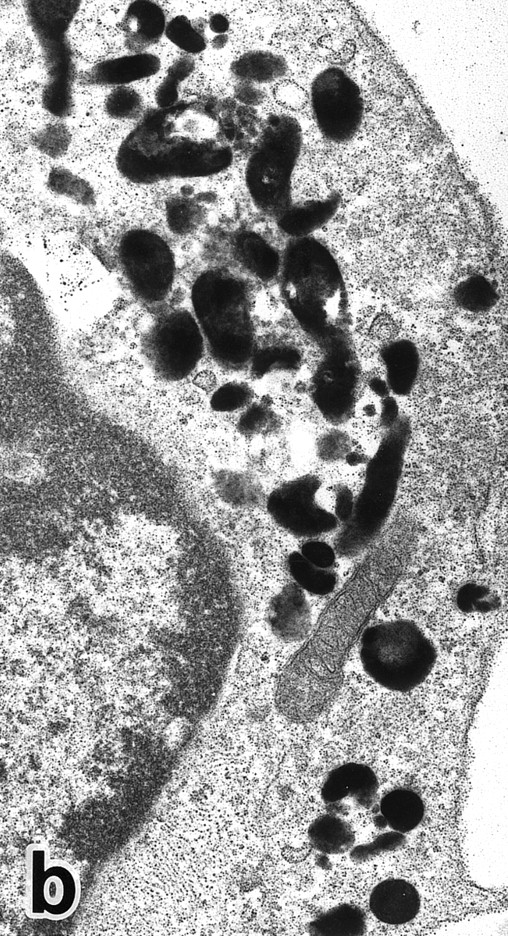

(a) A PMN in patient no. 1 after 1 week of ATRA treatment. Lobulated nuclei with a nuclear bleb (arrow) is seen. rERs are still dilated. Note that the primary granules have become normal in both size and shape and that neither Auer rods nor irregularly shaped inclusion bodies are seen in this cell. (Original magnification × 16,900.) (b) Higher magnification of the cytoplasm of another cell in patient no. 1, showing a structure in which a spherical primary granule (arrow) and an Auer rod are coupled. (Original magnification × 40,000.)

Common morphological changes of bone marrow leukemia cells were observed during ATRA treatment. After 1 week of ATRA treatment, leukemic cells showed heterochromatin condensation and nuclear lobulation (Figs 3 and 4). Although the lobulated nuclei of some cells resembled those of PMNs, these nuclei were irregular in shape and nucleoli were occasionally present. The lobulated nuclei often had nuclear blebs (Fig 3a) or were connected by thin nuclear material (Fig 4a), called filamentous connections,13 that consisted of heterochromatin delimited by the nuclear membrane. In addition to these changes, the irregularly shaped primary granules became morphologically normal. This was most evident in patient no. 1, in whom the majority of both Auer rods and irregularly shaped inclusions, as shown in Fig 2, dramatically vanished and the remaining primary granules appeared normal, being spherical in shape and relatively homogeneous in size (Fig 3a), although abnormal primary granules and/or Auer rods were infrequently observed in some cells. Rarely, a structure composed of an Auer rod coupled with a primary granule was found, appearing as though the seemingly normal primary granule had emerged from the Auer rod (Fig 3b). Type I primary granules still predominated in all patients, but type II primary granules with a nucleoid structure were rarely observed in patients no. 1 and 2. Some maturing neutrophils with abnormally shaped lobulated nuclei in patient no. 2 possessed unusual, possibly immature, primary granules containing central electron-dense material (Fig 4a and b), indicating asynchronous maturation of nuclei and cytoplasmic granules.